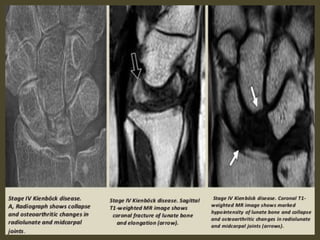

Keinbock,s Disease.